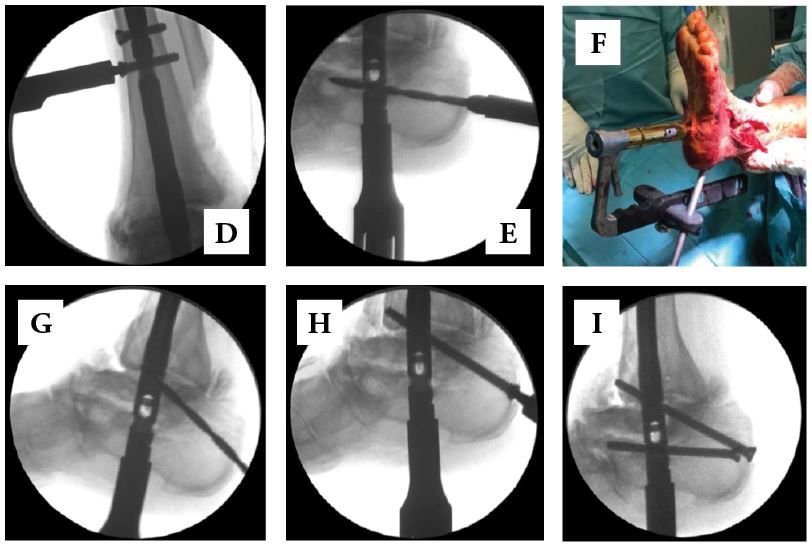

• Having rotation optimized, remove the guidewire, then transfix the nail with interlocking screws (Figs. 10-A to 10-I). The leg is held-up by the assisting surgeon in order to avoid conflicts of the nail holding sleeve with the operation table which could lead to undesirable rotational changes of the nail.

• Proximal screw is placed by the screw aiming guide from medial to lateral

• Proximal calcaneal screw is placed from lateral-to-medial.

• Remove the temporary fixation wires

• Achieve compression by advancing an intramedullary pre-loaded internal compression mechanism that translates the lateral-to-medial Calcaneal Screw to the top of the Compression Slot, thereby achieving compression of both the subtalar and ankle joints, as well as locking the Compression Screw into position.

• Radiographs are taken to confirm translation and compression

• Dorsoventral screw is inserted with the screw aiming guide at the calcaneus, which allows additional stability

• An additional subtalar screw might be inserted from lateral calcanear to medial talar which allows additional rotational stability in bad bone quality

• A proximal interlocking screw is inserted to allow dynamization for possible delayed bone healing

• Placement of interlockig screw through the joint space is ineffective and must be avoided (Fig. 10-C). Alternatively, relying on other interlocking screws can be sufficient